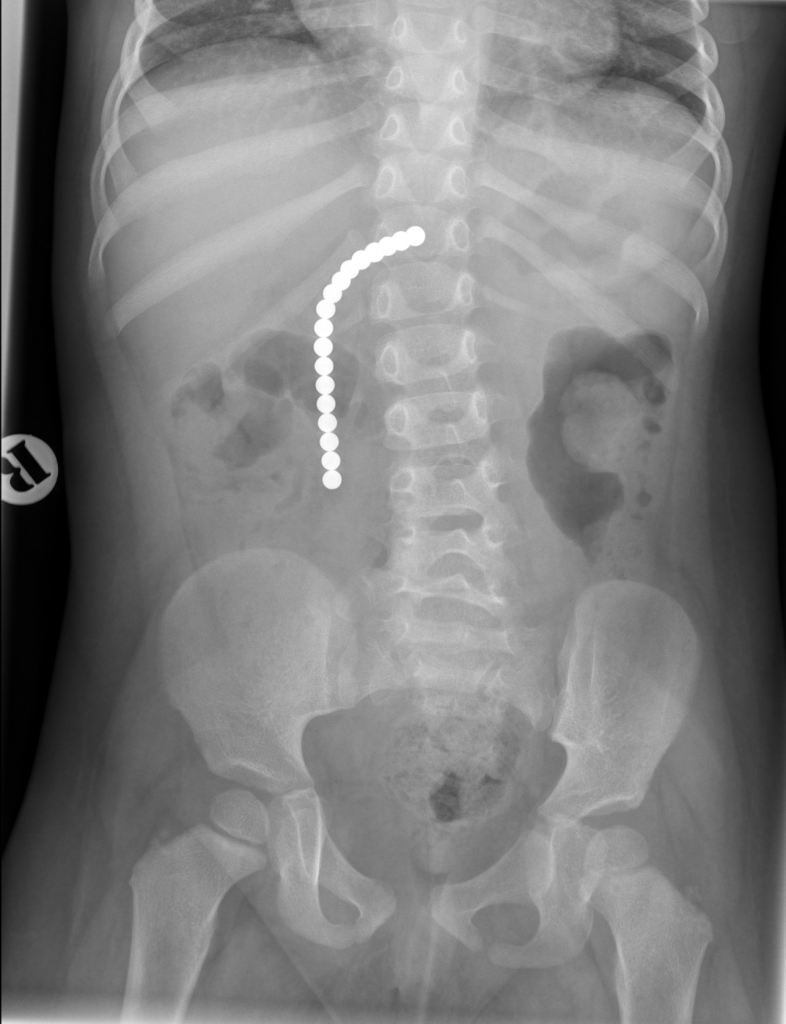

20. Magnets

If a child swallows small magnets, the terrifying thing is that they can stick together and trap and compress portions of the bowel wall between them. This could potentially lead to perforation, ischemia, sepsis and bowel obstructions. Keep magnets of any kind away from kids and pets, making sure you keep a close eye on children's toys that may involve magnets.